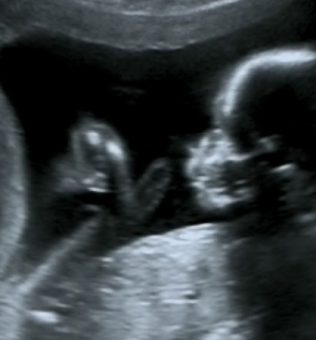

Etiqueta: EcografA�a